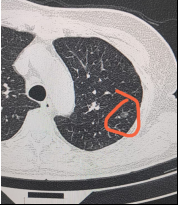

三、肺部磨玻璃结节真正长大

这种情况发生率不高,很多短期内快速增大的结节,反而更高概率是炎症性病变,真正是肿瘤性病变的磨玻璃结节,一般不会短期内内快速增大。

当然,我们举例针对的是邻近手术切除边界的肿瘤,平时遇到的误差导致的原因,遇到具体情况还需到专科进一步检查诊治。不可盲目对比。